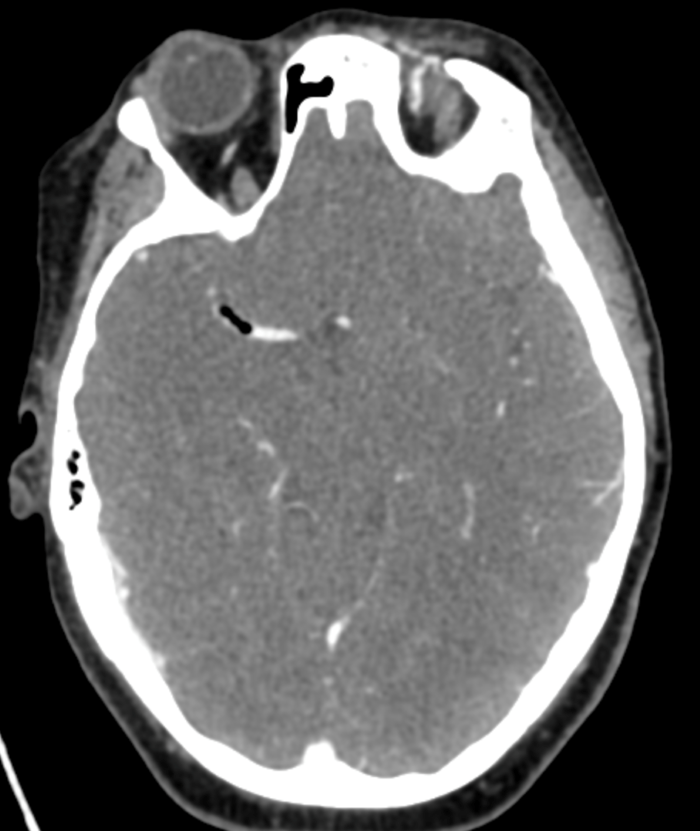

Initial objective data included T 37C, HR 85, RR 20, BP 153/109, spO2 98%. Glucose 102. Basic labs obtained and were unremarkable. Patient was rapidly taken to CT for stroke imaging. No contraindications to thrombolytics were identified. At 1708, noncontrast head CT showed no hemorrhage, but an abnormal hypodensity along the right middle cerebral artery concerning for an air embolus was visualized. CT angiogram head and neck was also suggestive of air embolus and CT perfusion brain demonstrated 27 mL of critical hypoperfusion at the right posterior middle cerebral artery distribution.

Figure 2: CT angiogram Head/Neck showing air in the R MCA